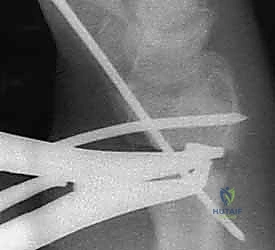

3. قص العظم التصحيحي (The Osteotomy)

بناءً على التخطيط الثلاثي الأبعاد المسبق، يستخدم الدكتور هطيف مناشير عظمية دقيقة جداً لعمل شق في العظم في نقطة التشوه الأصلية. يتم فتح العظم وتعديل زاويته واستعادة طوله الطبيعي.

5. التثبيت بصفائح التيتانيوم (Internal Fixation)

للحفاظ على الوضع الجديد والمثالي للعظم، يتم استخدام صفائح تيتانيوم متقدمة ذاتية الغلق (Volar Locking Plates). هذه الصفائح مصممة تشريحياً لتلائم شكل الكعبرة، وتوفر تثبيتاً قوياً جداً يسمح للمريض ببدء تحريك أصابعه في اليوم التالي للعملية.